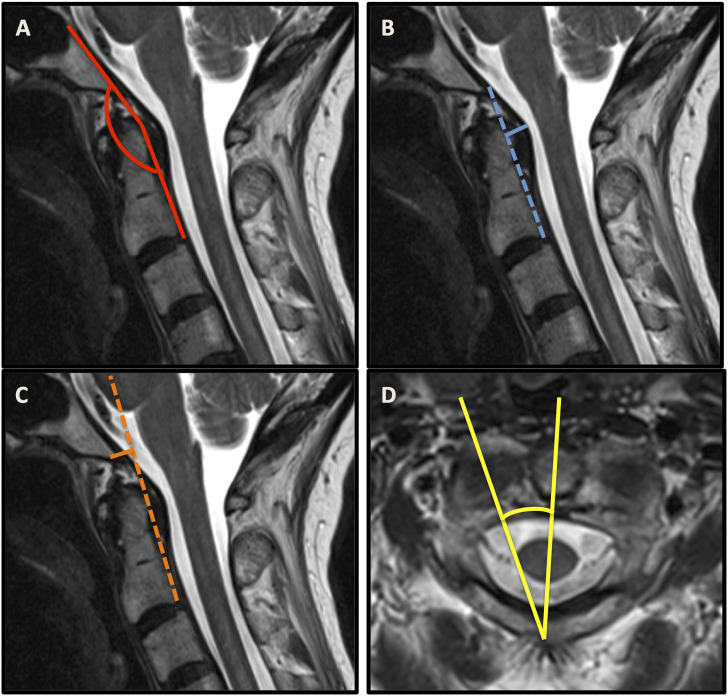

The most applied radiographic metrics to define CCI were the clivo-axial angle (CXA), the Harris measurement, the Grabb-Mapstone-Oakes measurement, as well as the angular displacement of C1 to C2 (Figure 2). The choice of diagnostic parameters was inconsistent in the majority of studies.

Figure 2.

Sagittal MRI sequences containing the clivo-axial angle (CXA) (A), the Harris measurement (B), the Grabb–Mapstone–Oakes measurement (C). Axial MRI sequence illustrating the angular displacement of C1 to C2 (D).

Henderson et al. reported 2 studies using the clivo-axial angle (CXA), the Harris measurement, and the Grabb–Mapstone–Oakes measurement as reliable indicators for CCI.11,13 The CXA was used repetitively to indicate potential brainstem deformity related to CCI. It describes the extent of kyphosis at the cranio-cervical junction being associated with pathological bending of the brainstem, which may result in mechanical injury and chronic damage to the lower brainstem and upper spinal cord.11,16,17 Equally, Spiessberger et al. referred to the CXA when assessing the outcomes of 2 different fusion techniques in EDS patients with CCI and cervico-medullary syndrome. They also used the Grabb–Mapstone–Oakes measurement (pB-C2 line) and confirmed improvement of both parameters regardless of the type of fusion technique, advocating for their value as surgical outcome parameters. 12